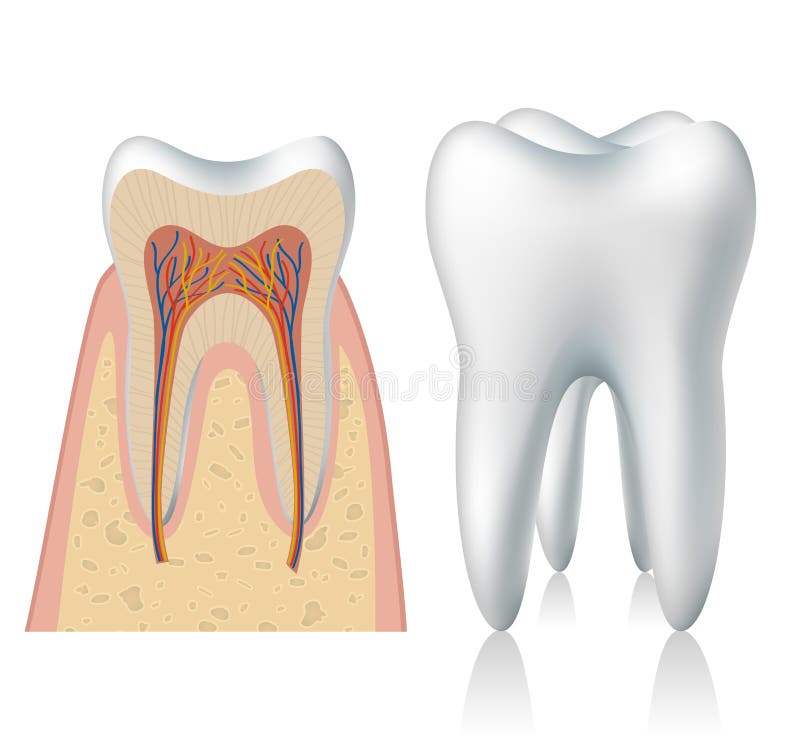

Tanden strukturerar Medicinskt diagram av strukturen av det inre tvärsnittet av tanden